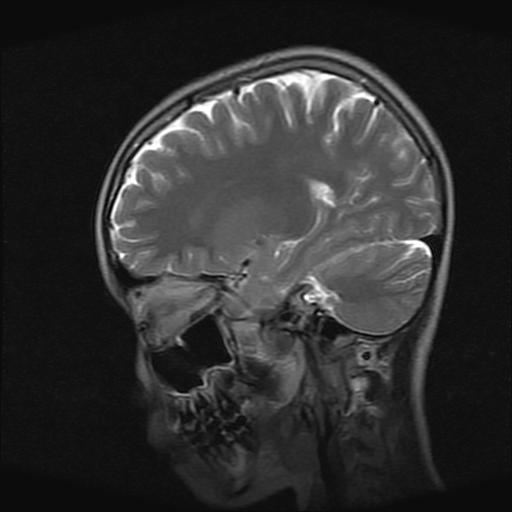

标题: PED0378:女孩9岁,癫痫,看能否停药 [打印本页]

9岁女孩,三岁时诊断为癫痫,一直服丙戊酸钠,现患者一般情况良好,家长复查核磁片,看能否停药..

巨脑回

停药要结合临床,如无发作可以停。

停药要结合临床,如无发作可以停